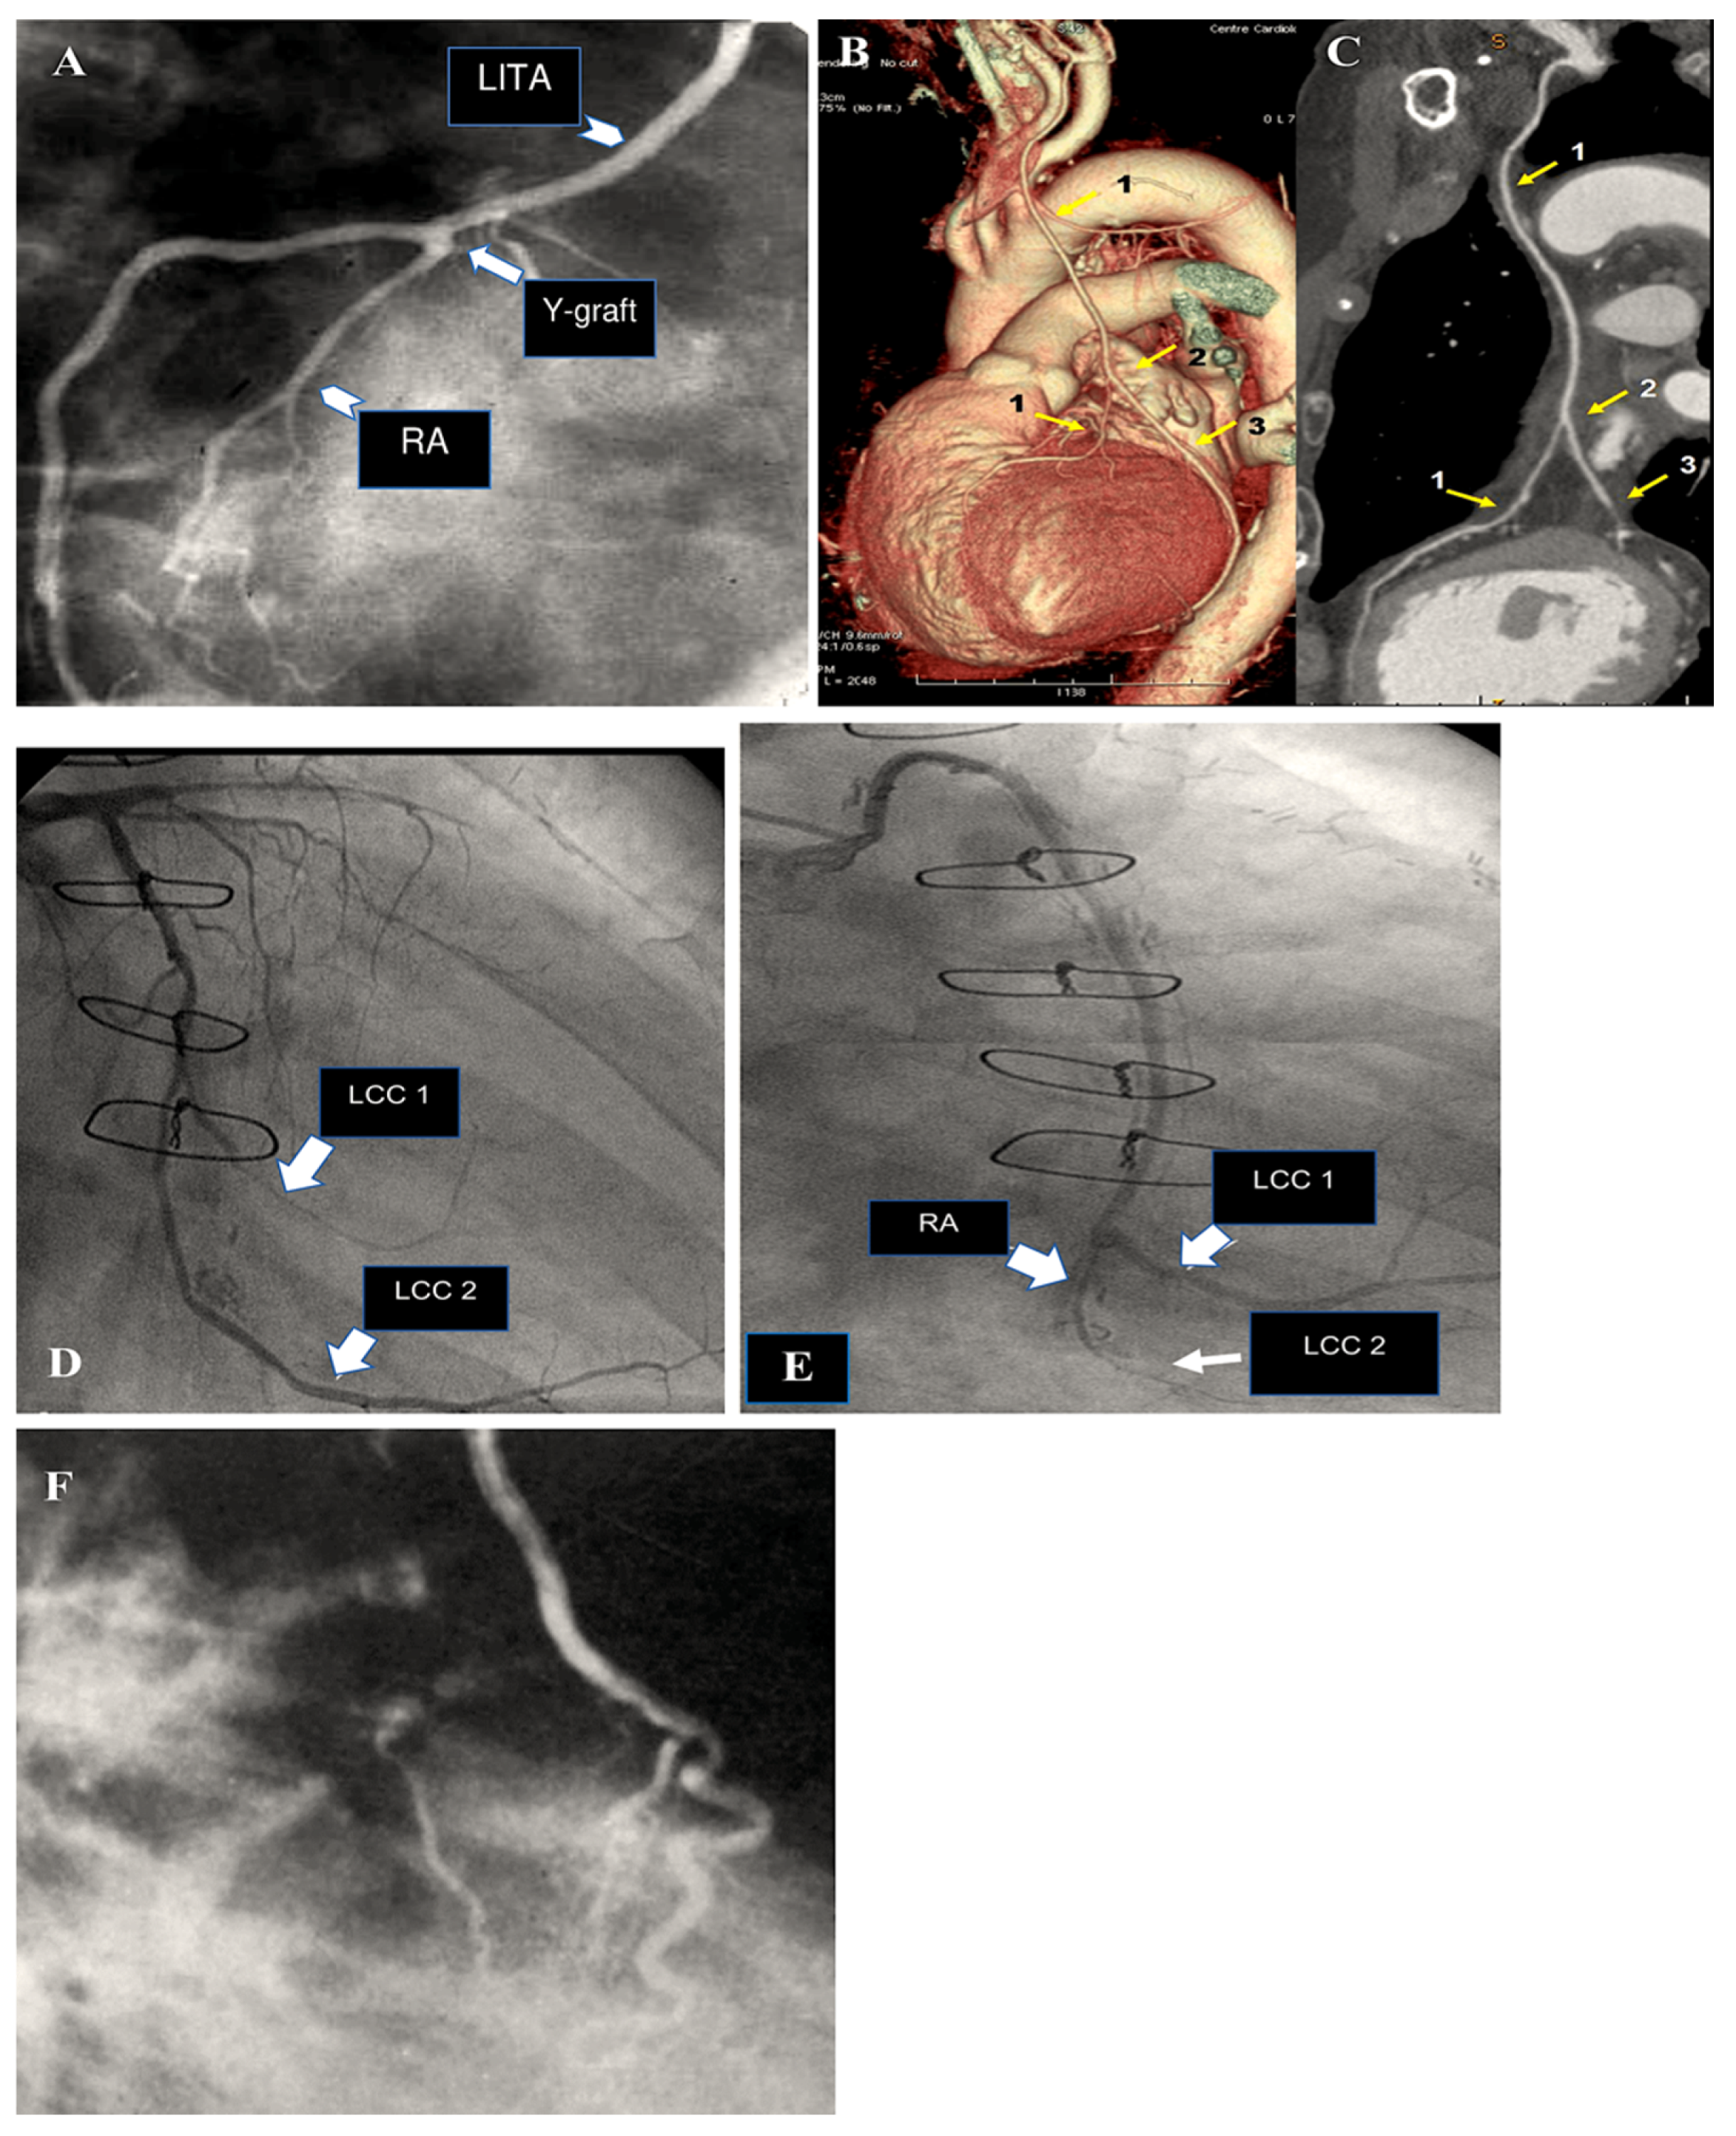

The results of a most recent investigation into our experience of radial artery grafting, comprising 819 patients, revealed that the five-year, ten-year, and fifteen-year survival rates were 95%, 81%, and 70%, respectively (Figure 5) [9,10,11,12,13].

Figure 5.

This shows how the radial artery can be used for CABG, either in a Y-shape for sequential grafting or for isolated grafting (A–F). (A): The RA is still open after five years. RA is used as a Y-graft technique for sequential anastomoses. (B,C): Y-graft technique on LAD and LCC2 at 6 years. (D,E): The blood flow is competitive, which causes the distal segment of the RA to shrink. The RA graft was anastomosed to the first and second obtuse branch of LCC at 8 years. (D): The circumflex coronary artery is free from significant narrowing, allowing unrestricted flow to the second obtuse branch. The first obtuse marginal is hardly visible. (E): The RA supplies the first obtuse branch (LCC1) with a string-like involution of its distal segment and no opacification of the second obtuse branch. (F): RA grafted on LAD and controlled at 18 years. Yellow arrow: 1. LITA; 2. Y-graft; 3. RA (LCC2). Abbreviations: CABG, coronary artery bypass grafting; LAD, left anterior descending; LCC, left coronary circumflex; LCC1, first obtuse branch; LCC2, second obtuse branch; RA, radial artery; RCA, right coronary artery.